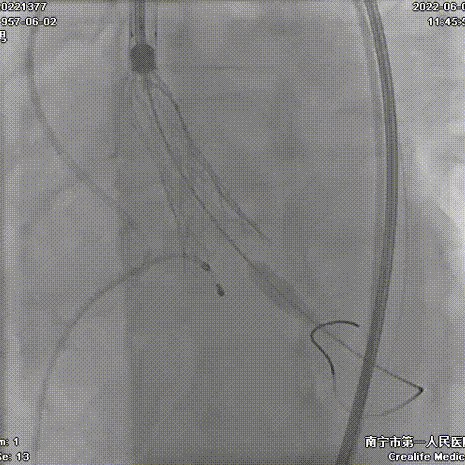

手术过程:

AV26瓣膜释放到工作位

AV26瓣膜释放

22mm球囊后扩

术后主动脉根部造影,形态改善

刘杰主任团队通力配合、精准释放,充分利用TaurusElite可回收功能,在瓣膜释放至2/3时,多角度评估瓣膜植入深度、锚定力以及冠脉灌注情况,确认瓣膜植入深度合适、锚定力稳定,缓慢逐个脱钩,进行瓣膜释放。释放后造影显示钙化挤压严重,瓣膜膨胀不良,故选择球囊后扩,后扩后造影显示瓣膜膨胀良好,行血流动力学评估,跨瓣压差从术前220mmHg降至5mmHg,无明显瓣周漏,手术圆满完成。术后10小时拔管,第二天正常下床活动,术后5天出院。